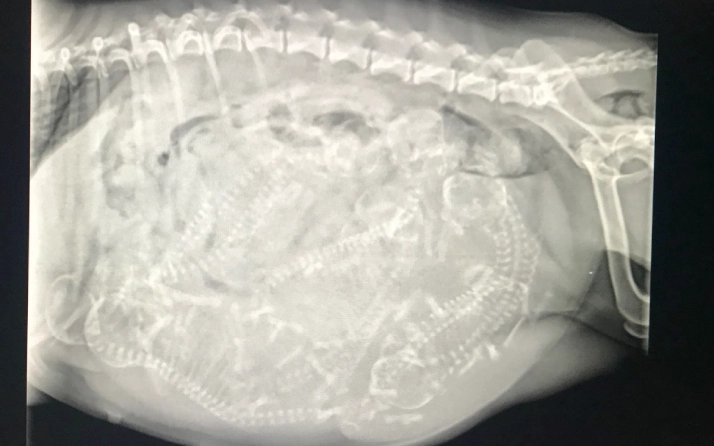

X-ray of a pregnant animal with fetuses.

This is an X-ray of Goose's pups at about 50 days pregnant. You should be able to count 7 spines and 7 skulls.